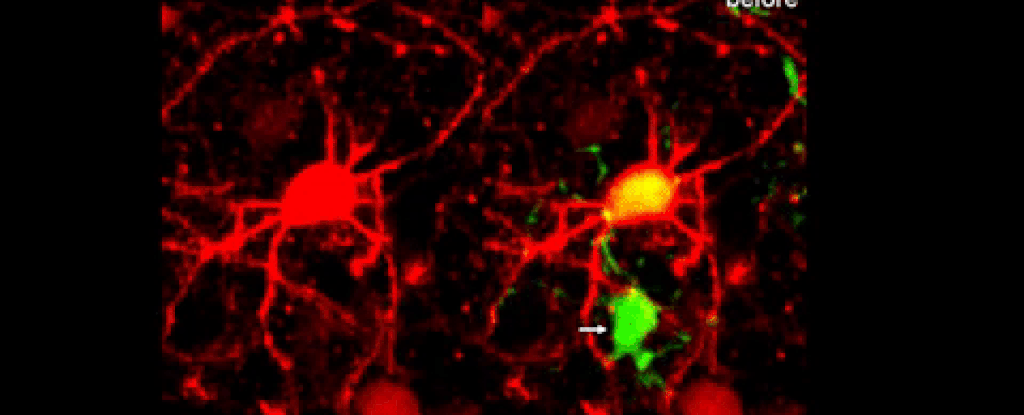

Het efficiënt opruimen van dode cellen is cruciaal voor onze gezondheid. De onderzoekers laten zien hoe dat in de hersenen van muizen eruit ziet. Als eerste is te zien hoe microgliacellen de dode neuron omringen en dan opslokken. Andere hersencellen, genaamd astrocyten, ruimen de aftakkingen (dendrieten) van de neuronen op. Vervolgens zorgen de NG2-cellen ervoor dat het celafval zich niet verspreidt in de hersenen. Opvallend was dat de hersenen van oudere muizen dit proces minder efficiënt uitvoerden.

neurondeath 1024